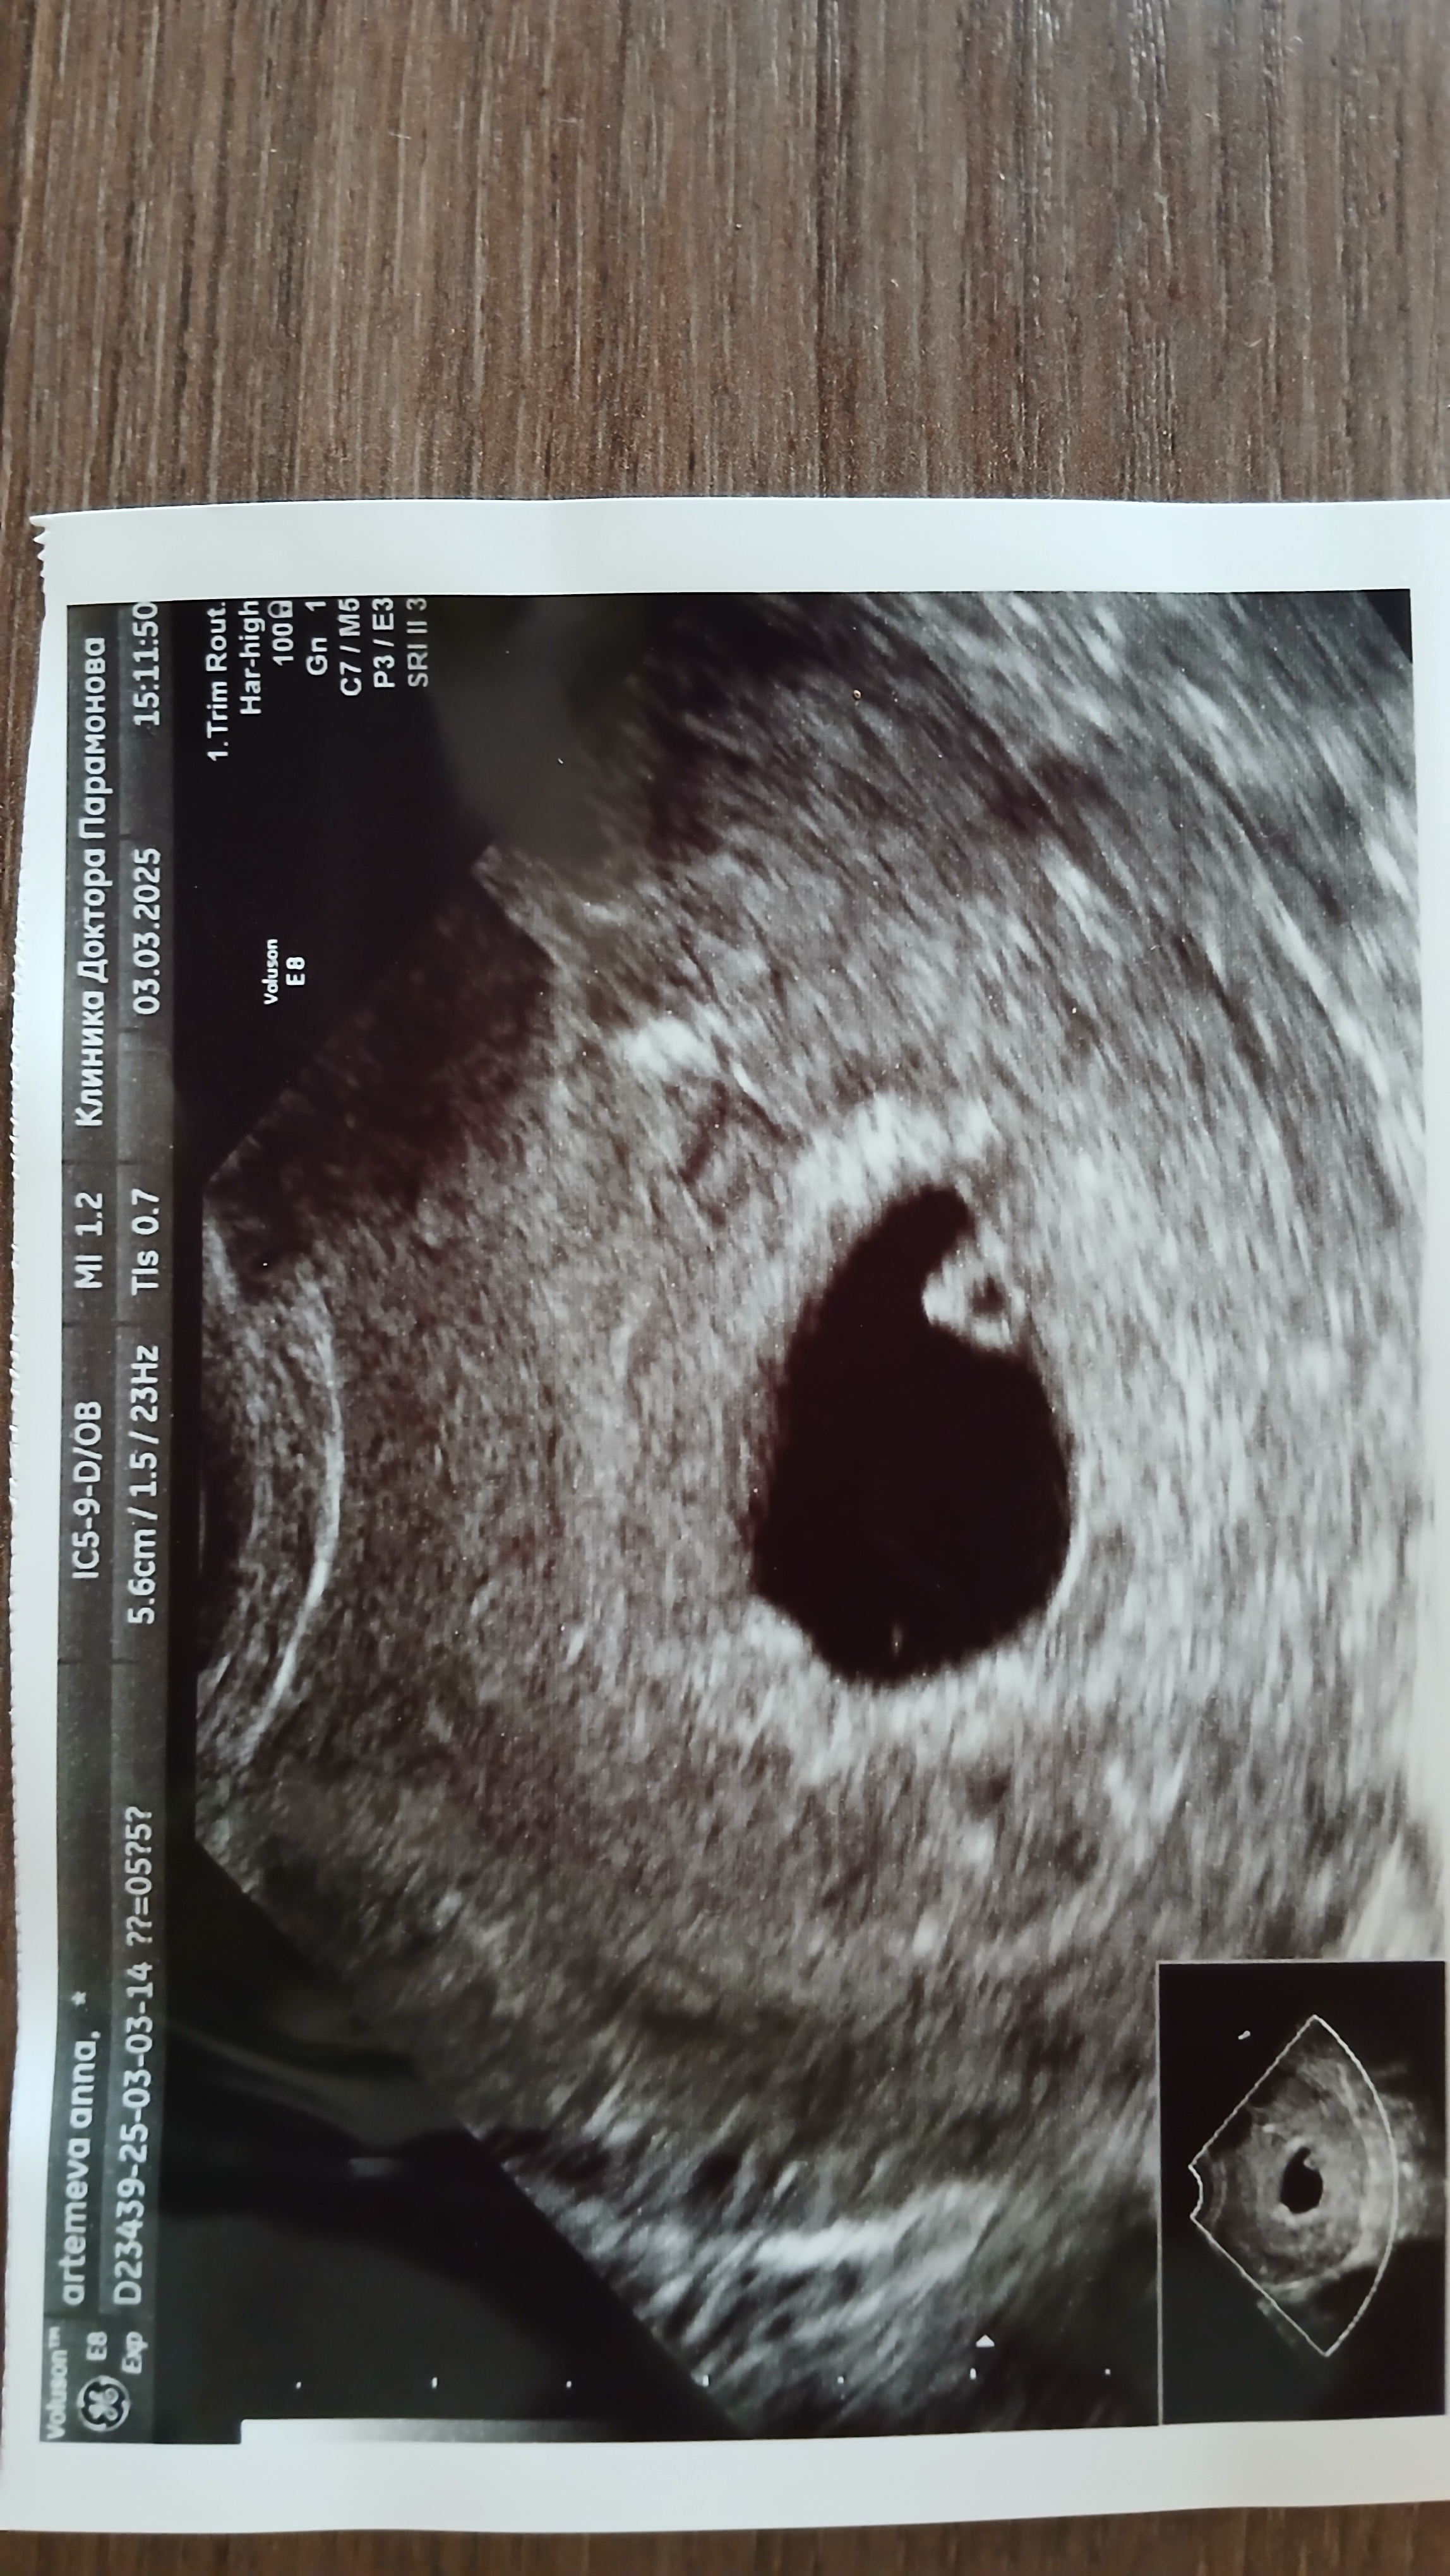

Анна в Зачатие 9 месяцев Первое УЗИ-всё хорошо🥰 УЗИ Было волнительно... всё видно и слышно,сердечко стучит🥰 Моё колечко драгоценное💍 Посмотрите еще 20 записей на эту тему Лучший ответ Надежда Ох так приятно видеть такие посты 🤰😊 Поздравляю 🌺😊 03.03.2025 Ответить Анна Надежда , спасибо огромное🥹🫶 04.03.2025 Ответить Отменить Ответить Узи овуляции Начинаем готовиться к Б Чаты Беременных Выберите чат: Январята-2026 Февралята-2026 Мартята-2026 Апрелята-2026 Майчата-2026 Июнята-2026 Июлята-2026 Августята-2026